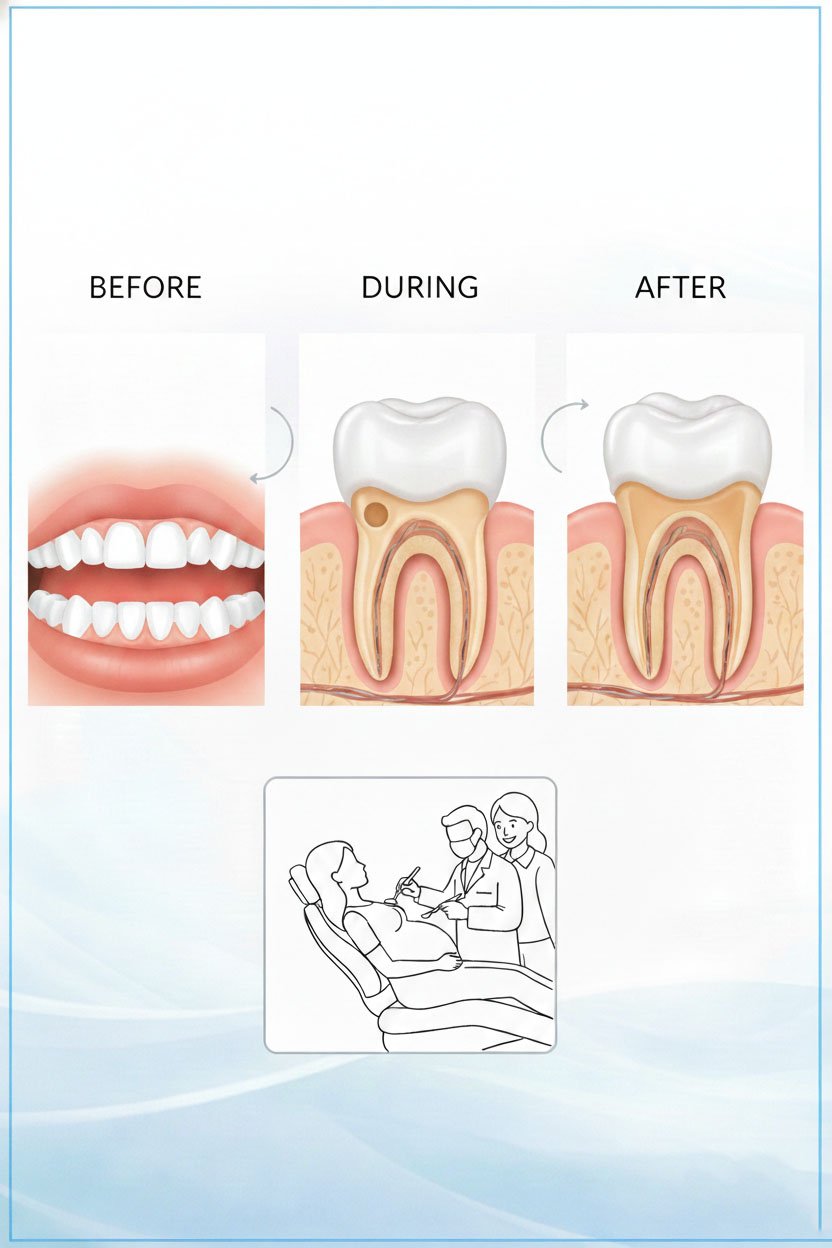

Pain-Free Single Sitting RCTs